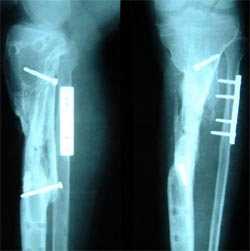

以上图片为三位患者的X线片,显示股骨粗隆下骨折、骨不连,内固定已经失败。

主要采用股骨重建髓内钉获得良好早期的稳定性,为骨愈合创造条件,

有的病例采用DHS治疗,同时采用骨髓细胞和植骨复合物植入。成功治愈患者。